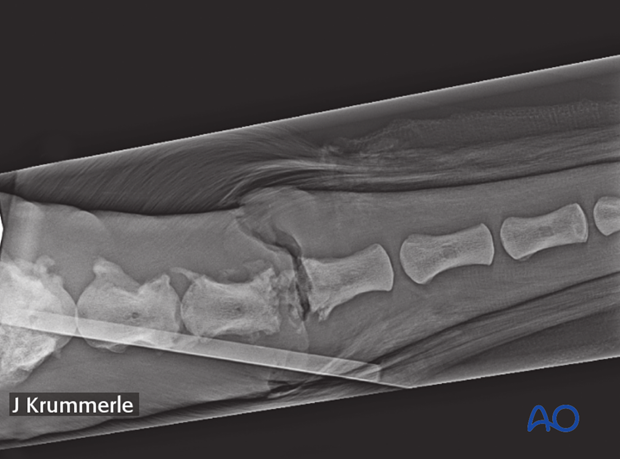

Lateral or oblique lateral radiographs confirm the presence of a vertebral fracture.

22-year-old warm blood with an open infected fracture in Co7.

Lytic and proliferative lesion of the coccygeal vertebra.